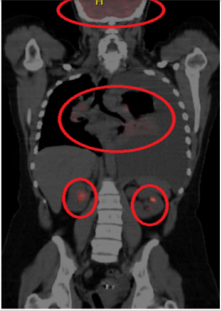

It showed evidence of stage IV adenocarcinoma with immunohistochemistry positive for anaplastic lymphoma kinase (ALK-D5F3) in the neoplastic cells. Oncology service was notified, and the patient was scheduled for outpatient chemotherapy. A follow up magnetic resonance imaging of the brain (MRI) showed multiple scattered enhancing masses situated along the gray-white interface throughout both cerebral hemispheres compatible with metastases (Figure 2). Nuclear medicine positron emission tomography (PET)/ CT scan of the skull to thigh showed multiple hypermetabolic areas suspicious for neoplastic process and metastases including the right supraclavicular lymph node, left perihilar region, right posterior lateral chest wall/rib cage, right anterior chest wall/subpectoral region, right lower anterior abdominal wall and right medial thigh. Moreover, it showed hypermetabolic liver lesion concerning for liver metastases and scattered skeletal hypermetabolic lesions suspicious for osseous metastasis including lytic sclerotic lesion in the left proximal femur (Figure 3). Taking into account her ALK positive status, the patient was planned for therapy with Alectinib and was scheduled for pleurx catheter placement by thoracic surgery to manage her pleural effusions.

Figure 3: Nuclear medicine positron emission tomography of the skull to thigh showing multiple hypermetabolic areas suspicious for neoplastic process and metastases.